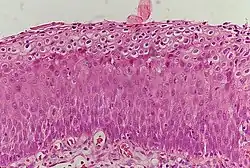

Normal cervical epithelium

Historically, abnormal changes of cervical epithelial cells were described as mild, moderate, or severe epithelial dysplasia. In 1988 the National Cancer Institute developed "The Bethesda System for Reporting Cervical/Vaginal Cytologic Diagnoses".[15] This system provides a uniform way to describe abnormal epithelial cells and determine specimen quality, thus providing clear guidance for clinical management. These abnormalities were classified as squamous or glandular and then further classified by the stage of dysplasia: atypical cells, mild, moderate, severe, and carcinoma.[16]

Depending on several factors and the location of the lesion, CIN can start in any of the three stages and can either progress or regress.[9] The grade of squamous intraepithelial lesion can vary.

CIN is classified in grades:[17]

Histology grade Corresponding cytology Description Image

CIN 1 (Grade I) Low-grade squamous intraepithelial lesion (LSIL)

• Mild epithelial dysplasia

• Confined to the basal 1/3 of the epithelium

• Typically corresponds to infection with HPV

• High rate of regression back to normal cells

• Usually managed expectantly